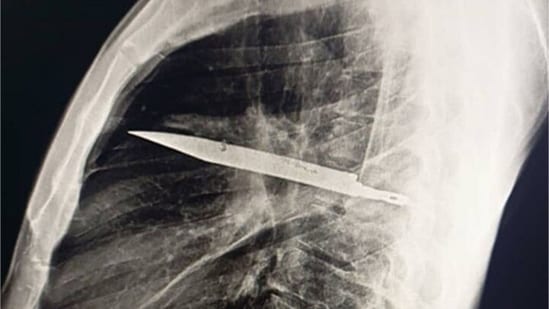

According to a case study published in National Library of Medicine on May 31, 2025, a 44-year-old man, who was 'otherwise healthy', sought medical care after his right nipple began leaking pus – and an X-ray revealed a knife lodged in his chest from an attack eight years earlier. Researchers said doctors were able to remove the knife and highlighted the need for imaging and follow-up treatment. Also read | This CT scan belongs to ‘a 73 year old woman in whom doctors discovered a 30 year old calcified fetus' aka stone baby

This case of a Tanzanian man highlights the importance of proper medical care and follow-up treatment and illustrates how in low-resource areas, especially, access to medical care and follow-up treatment may be limited, leading to delayed diagnosis and treatment.

The fact that the knife remained lodged in the man's chest for eight years without causing more severe symptoms is remarkable. Sharing details of the case, doctors reportedly said, “A 44-year-old male Tanzanian presented to our facility with a 10-day history of pus discharge below the right nipple. He denied any chest pain, difficulty breathing, cough, or fever.”

They added, “The patient recalled being involved in a violent altercation 8 years ago, during which he sustained multiple cuts to his face, back, chest, and abdomen. Following the incident, he sought first aid at a primary health facility, where his wounds were sutured; however, no radiological investigation was conducted at that time as hemostasis was achieved, despite no suspicion of foreign body retention in the part injured, there were no facilities for radiological investigations. He had an uneventful course over the next 8 years until his current presentation.”

The case report stated: “Imaging performed during the current presentation revealed a retained knife blade within the right hemithorax. A right thoracotomy was performed, and the foreign body was successfully removed. The patient had an uncomplicated postoperative recovery.”

It added, “This case underscores the potential for significant delayed complications from untreated penetrating chest trauma, particularly in settings with limited access to definitive surgical care. Improved trauma management protocols, including enhanced initial evaluation and follow-up, are essential to prevent such long-term morbidity in resource-constrained environments.”